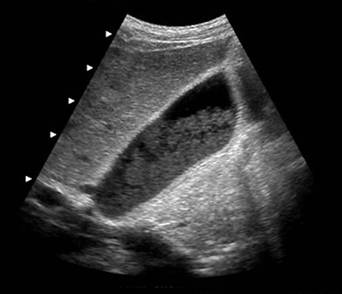

In obstructia biliara joasa, secundara unor tumori pancreatice cefalice sau ampulare si, mai rar, unor calculi coledocieni, la distensia colecistului (semnul clinic Courvoisier - Terrier) se asociaza dilatarea cailor biliare extra- si intrahepatice.

Obstructie biliara joasa (dilatare de CBP si moderata dilatare a CHIH)